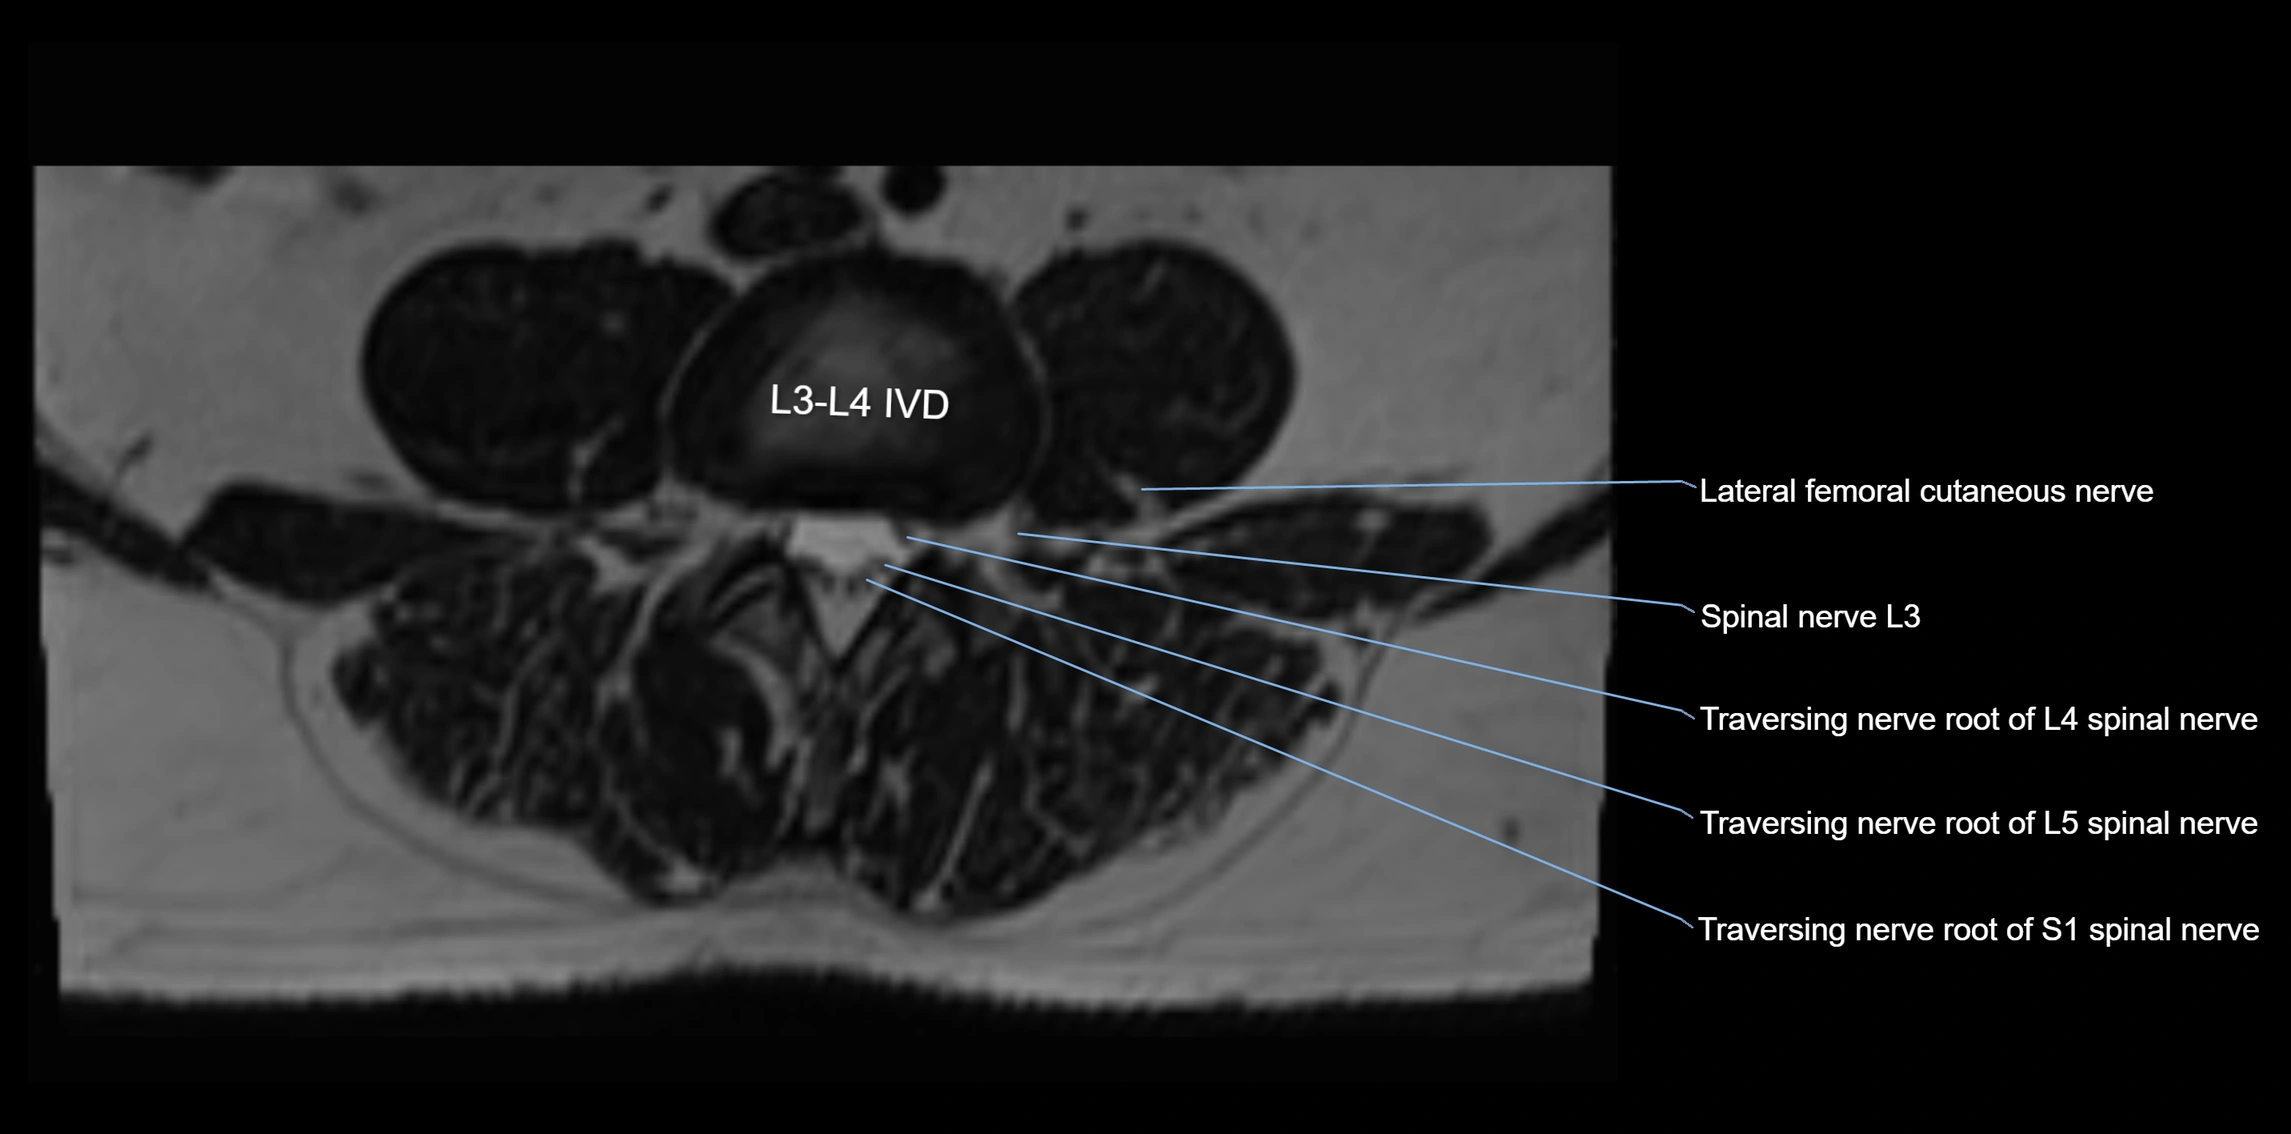

MRI Appearance

T1-weighted images:

• Nerve appears as a very thin low-to-intermediate signal intensity structure

• Surrounded by bright fat, aiding visualization

T2-weighted images:

• Nerve shows intermediate to mildly hyperintense signal compared to muscle

• Pathological involvement appears brighter

STIR (Short Tau Inversion Recovery):

• Normal nerve appears dark

• Inflamed or entrapped nerve appears bright hyperintense

T1 Fat-Sat Post-Contrast:

• Normal nerve enhances minimally

• Pathologic nerve (neuritis, entrapment, tumor infiltration) shows focal or diffuse enhancement

3D T2 SPACE / CISS:

• Nerve appears intermediate to mildly hyperintense compared to muscle

• Surrounded by bright fat or CSF, improving visualization

• Best sequence for mapping small pelvic nerves such as the anococcygeal